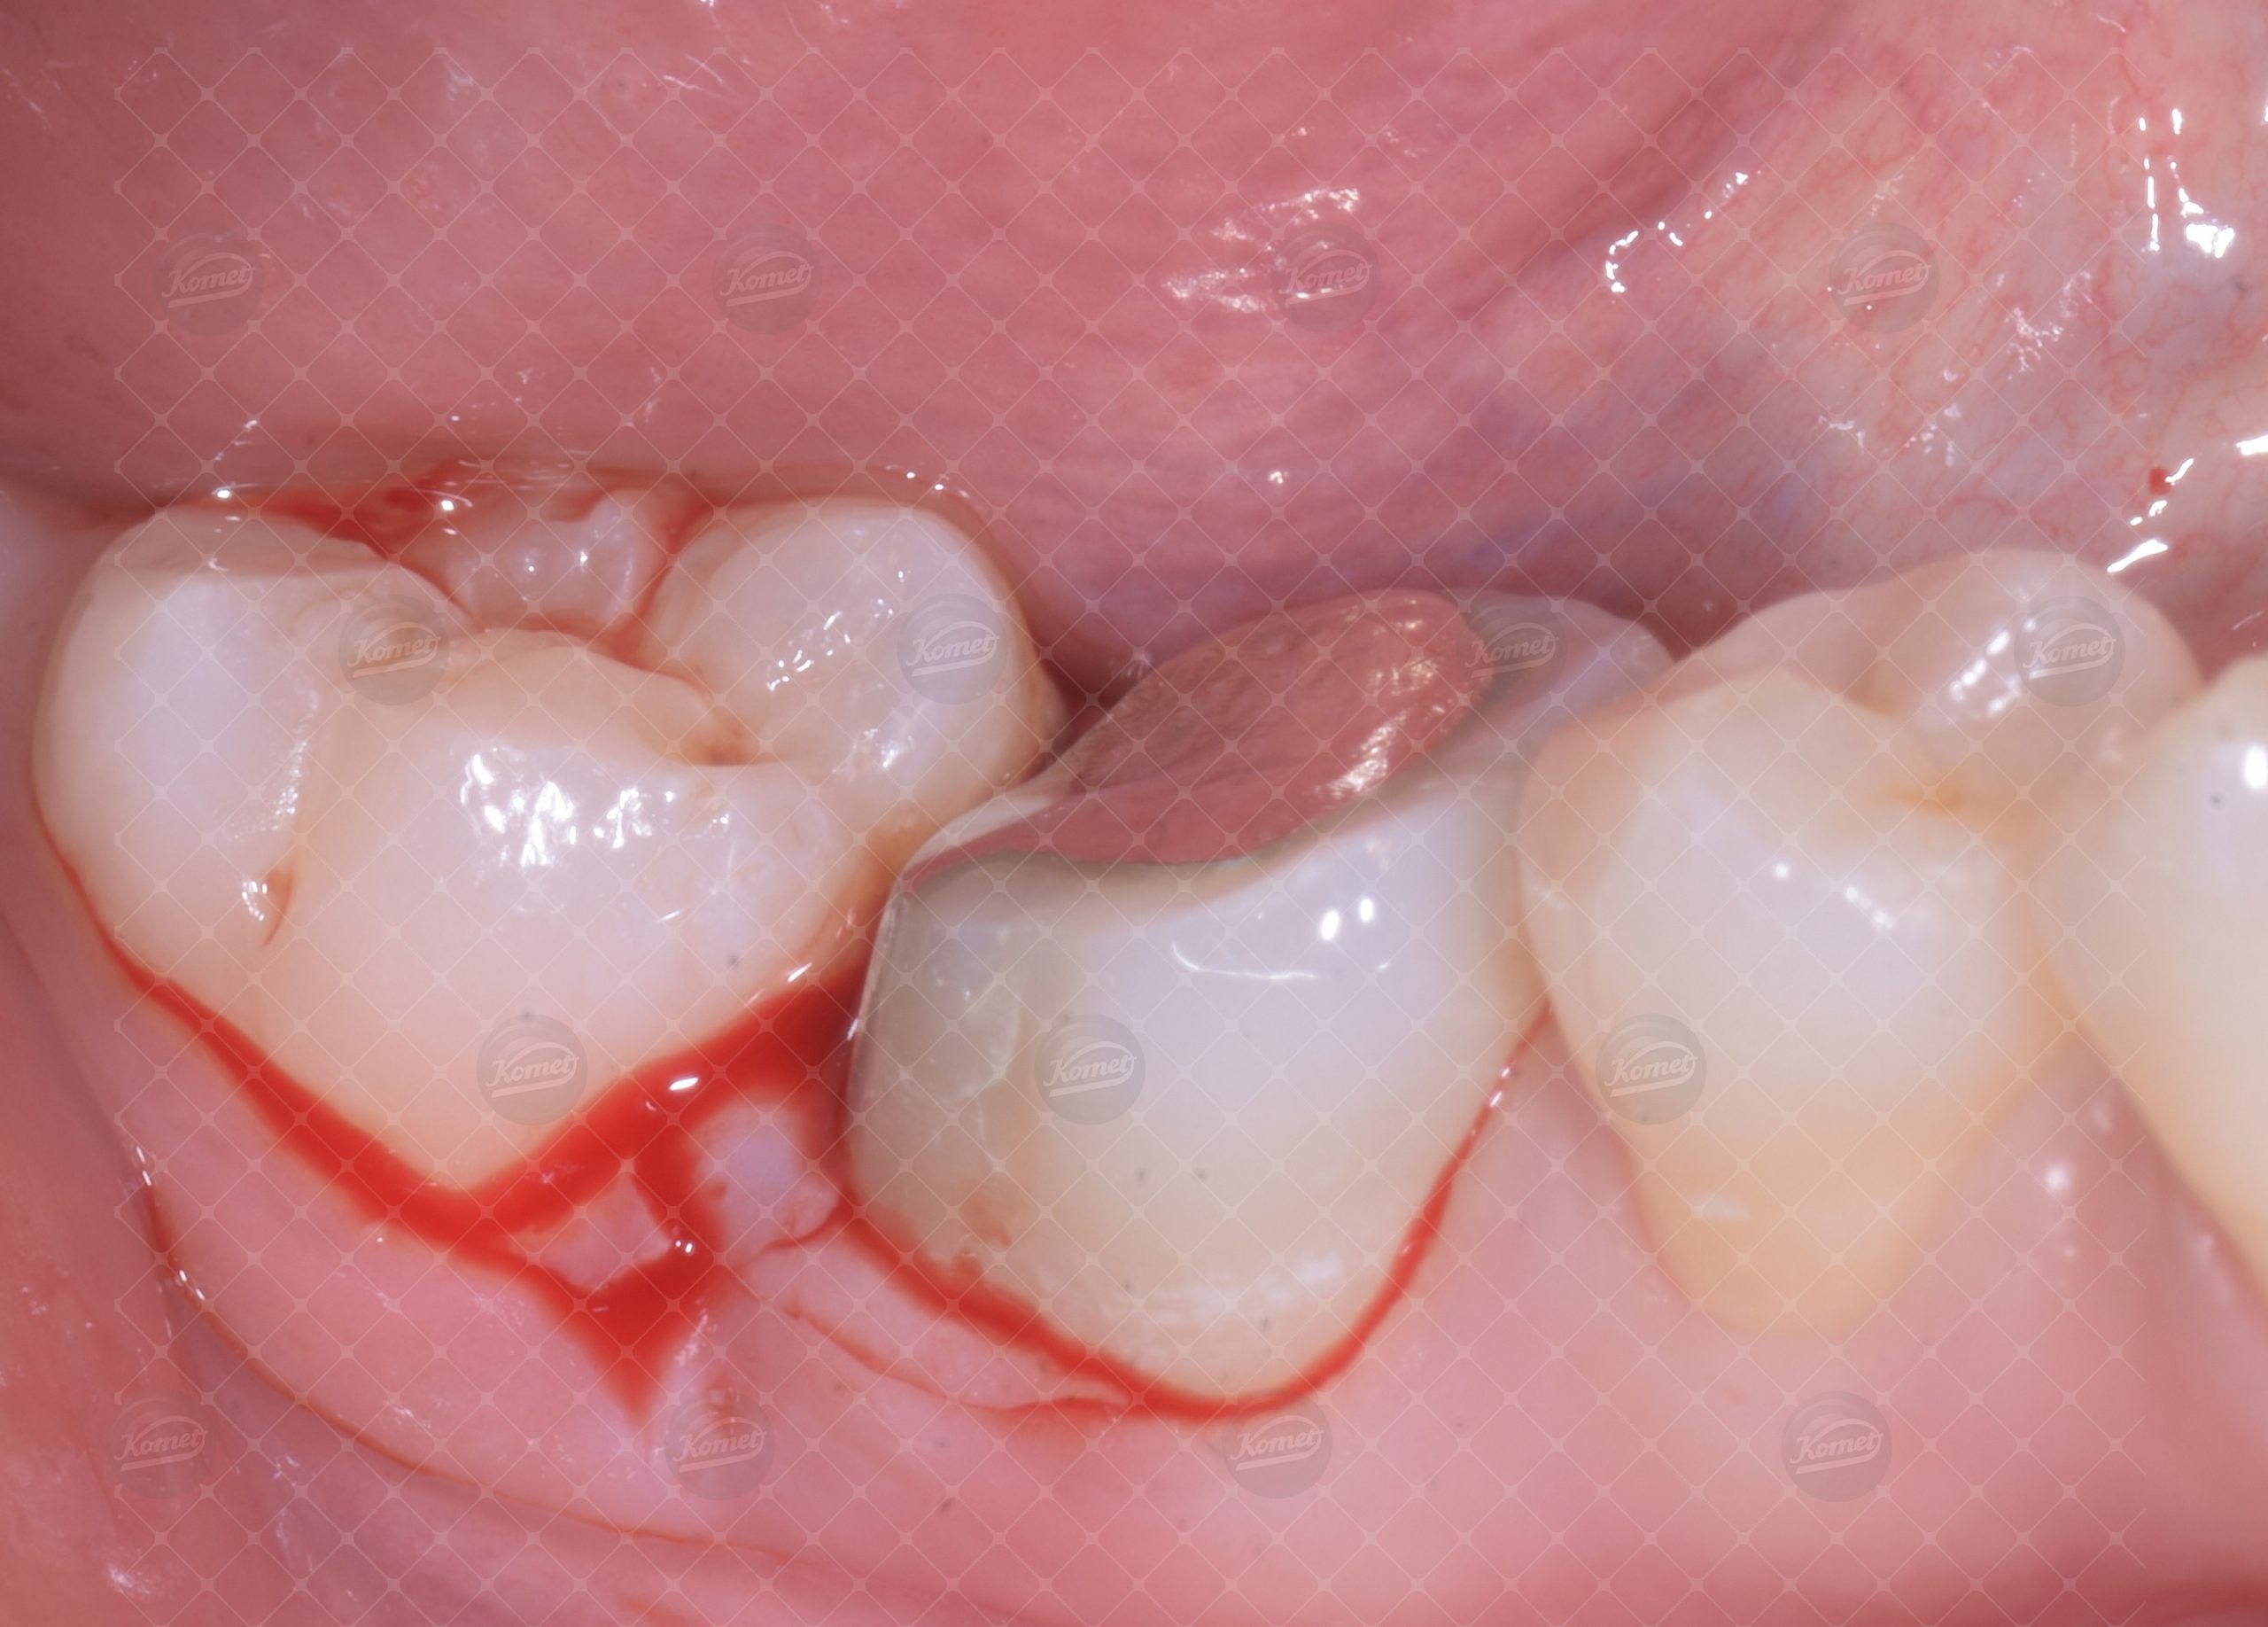

Al fine del recupero dell’elemento dentario, un primo molare del quarto quadrante è stato sottoposto a terapia endodontica e successiva ricostruzione con perno moncone in lega preziosa. La valutazione parodontale evidenzia una distanza dal margine di tessuto dentale sano al livello osseo marginale sul versante interprossimale distale di 2 mm, insufficiente a garantire il cerchiaggio con effetto ferula della futura corona protesica ne’ tantomeno a consentire il costituiti di una fisiologica altezza di ampiezza biologica (Fig 1,2).